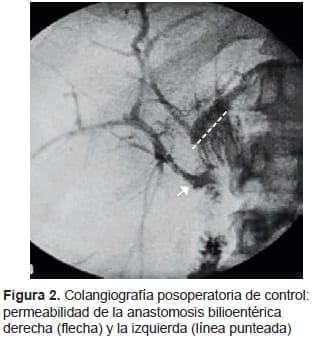

La evolución posoperatoria fue satisfactoria y se le dio egreso a la paciente al tercer día de

la intervención. En la colangiografía de control a los tres meses, se demostró la permeabilidad de la anastomosis (figura 2). A los doce meses de seguimiento, la paciente se mantiene en condiciones estables, bajo un esquema de control ambulatorio anual (examen clínico, pruebas de laboratorio y ultrasonido hepático).

Además, en el presente caso, se practicó una colangiografía percutánea intraoperatoria y se colocó un catéter en el conducto hepático derecho. Lo cual facilitó localizar esta estructura anatómica y exponerla durante el acto quirúrgico. Además de permitir el control radiológico posoperatorio (figura 2).